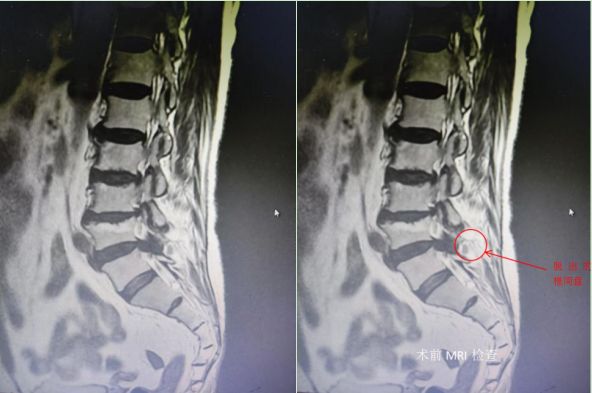

患者杨女士,现年61岁,受左下肢反复疼痛困扰已有5年,此次症状再发加重1月,疼痛剧烈,严重影响日常生活和工作,尝试过针灸理疗以及各种保守治疗方式,效果均不理想。入住大竹县人民医院骨科后,经完善相关检查,发现其腰椎多个节段均有较为明显的退变伴有椎间盘突出同时还合并有骶椎腰化改变。

骨科副主任唐洵仔细了解杨女士病史并细致查体、综合分析病情后,确定患者的责任节段为腰5/骶1节段椎间盘脱出所致,于是为患者制定了关节镜辅助单孔脊柱手术技术(AUSS)进行微创治疗的手术方案。术后患者疼痛即刻缓解,对整个治疗过程非常满意。